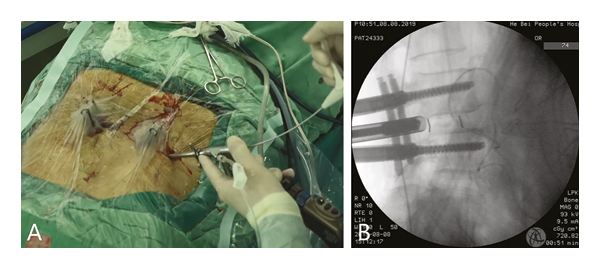

The pedicle screw placement procedures were completed by two senior spine surgeons who had each performed more than 50 cases of fluoroscopy-guided pedicle screw insertion. After general anesthesia, the patient was placed in a prone position. A C-arm was used to locate the targeted vertebral pedicles and plan the screw route. A puncture needle was inserted through a 1.5 cm incision with fluoroscopy guidance. After a final fluoroscopy check on the AP and lateral views, the puncture needle was replaced with a spacer. Screw (minimally invasive spinal system; WEGORTHO Paedic Device Co., Ltd.; Weihai, China) placement was performed after decompression and interbody fusion (Figure 4).

(a)

(b)